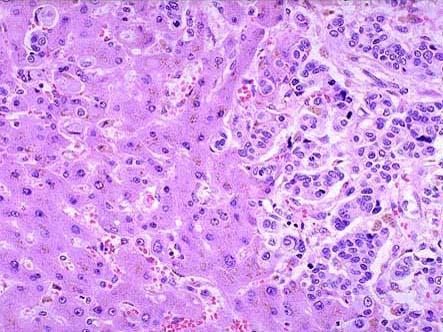

问题 死者,女性,76岁,死于晚期胃癌恶病质。尸检见肝脏表面多发性边界清楚结节如图,镜检如图所示,肝脏的正确病理诊断为 ( )

选项 A.结节性肝硬化 B.胃的转移性肝癌 C.肝转移性胃癌 D.肝脓肿 E.肝细胞性肝癌

答案 C